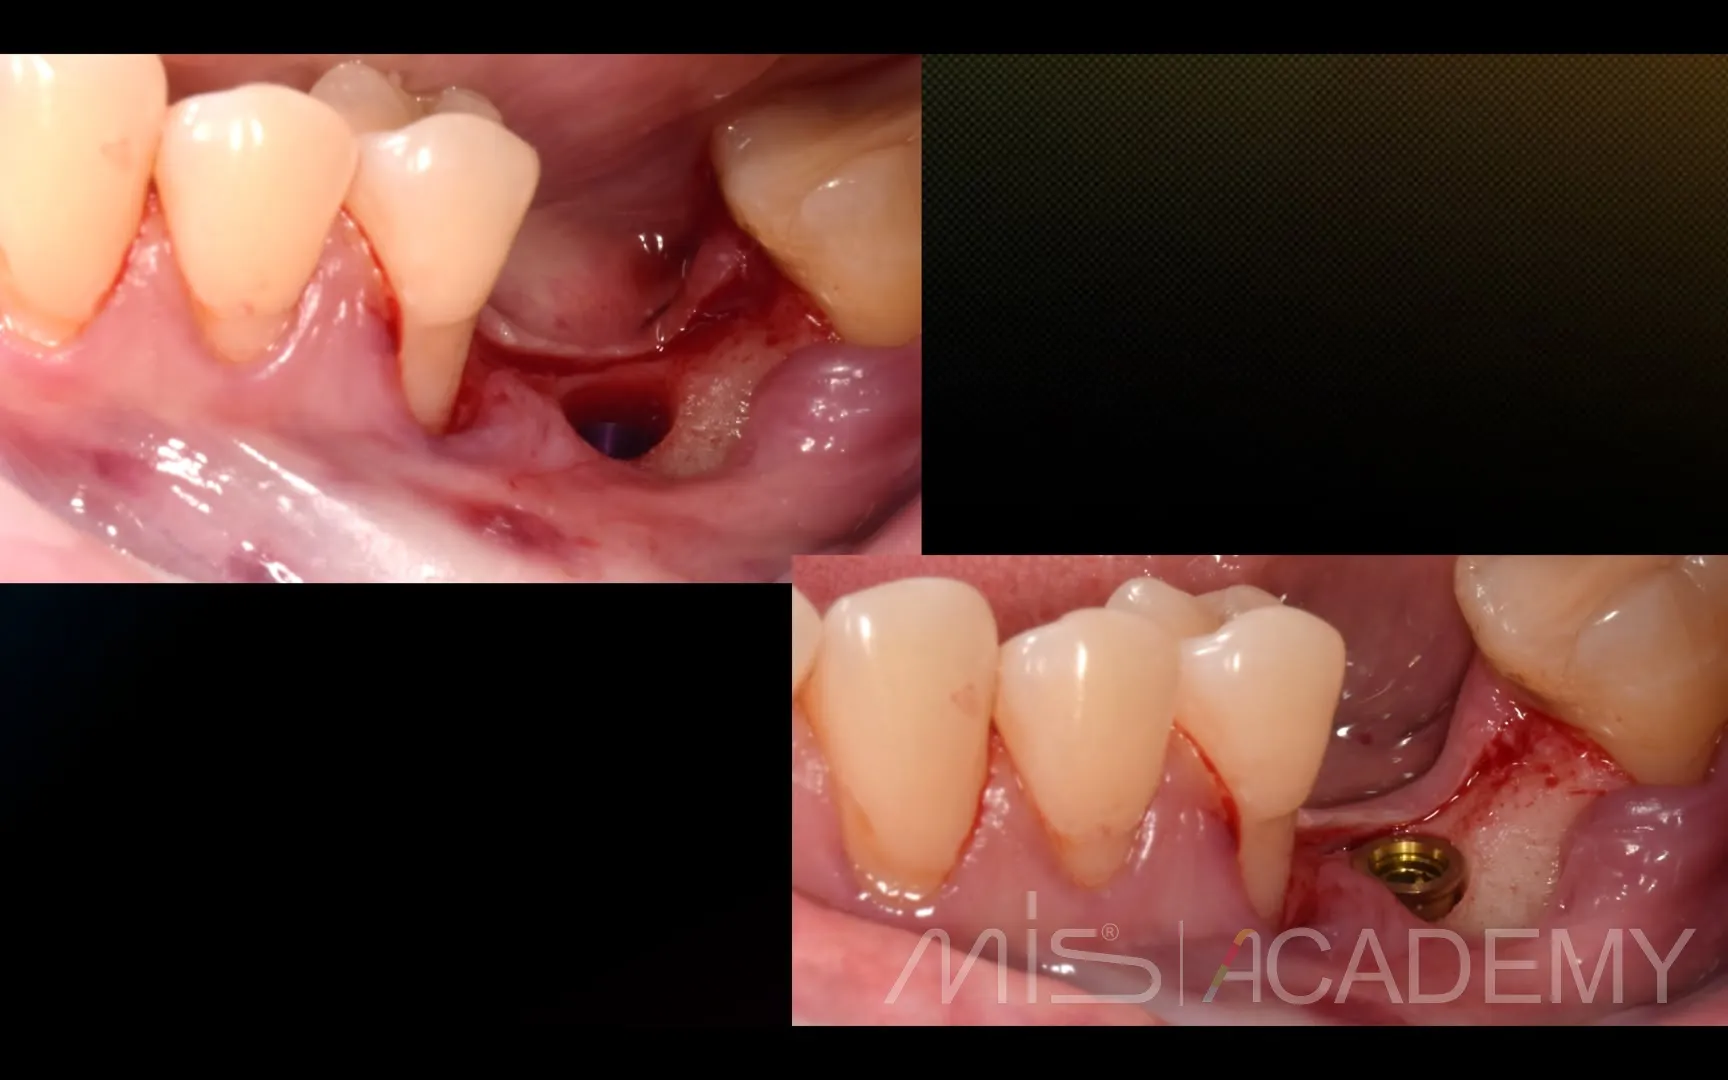

Промежуточный результат клинического кейса одномоментного закрытия рецессий и установки имплантата MIS C1 с CONNECT абатментом.